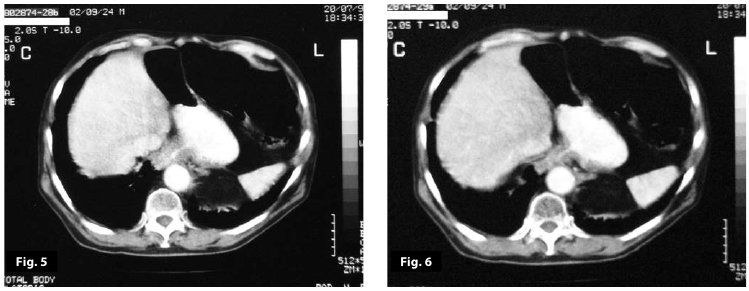

Figure1

Figure1-2

Figure1-2-3-4